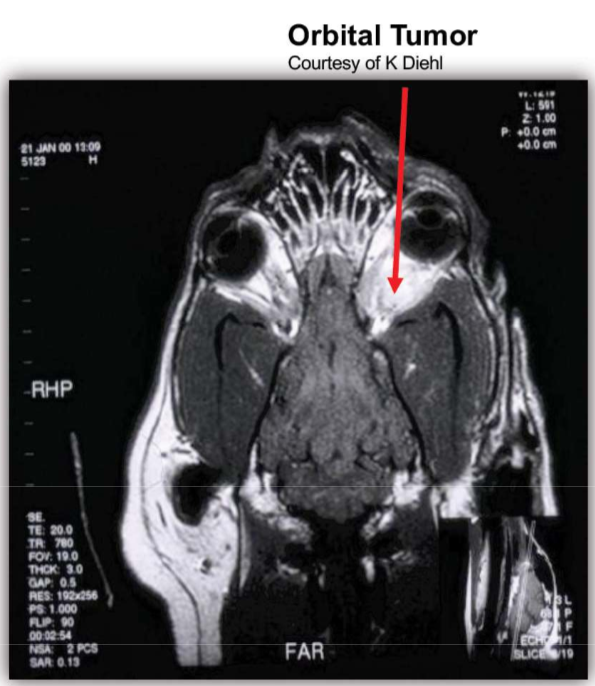

How useful are MRIs in diagnosing orbital disease?

• Requires general anesthesia

• Useful for:

• 3D orbital imaging

• Detailed soft tissue study

• Contraindicated with metallic foreign bodies

What are the clinical findings with Orbital Neoplasia

* Unilateral exophthalmos * Elevated third eyelid * Decreased retropulsion * Scleral indentation on fundic exam * Usually Not Painful

How are Orbital Neoplasias diagnosed?

* Complete physical exam * Thoracic radiographs (metastasis) * Orbital ultrasound * CT/MRI for lesion localization and surgical planning * FNA/biopsy of lesions